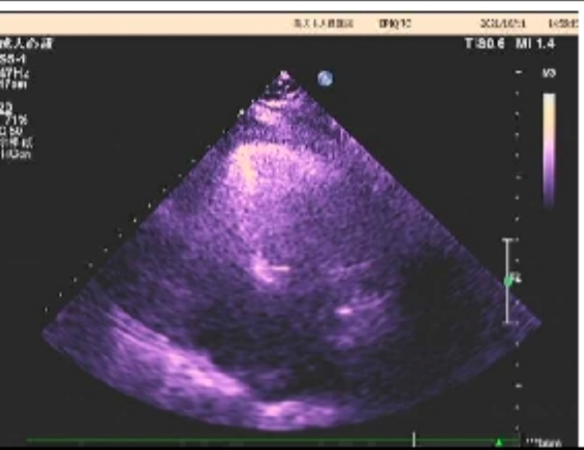

心脏彩超

主动脉瓣病变:主动脉瓣重度狭窄伴大量反流

峰值流速:4.8m/s;

平均跨瓣压差:53mmHg;

左室射血分数EF值:56%;

左室舒张末期内径(LVD):54mm;

左房增大,主动脉增宽,二尖瓣少量返流,左室舒张功能减退。

左室射血分数EF值:58%;

左室舒张末期内径(LVD):55mm;

主动脉瓣大量返流,左房、左室增大;

并左室壁增厚;

二尖瓣、三尖瓣及肺动脉瓣少量返流;

左室舒张功能减退。